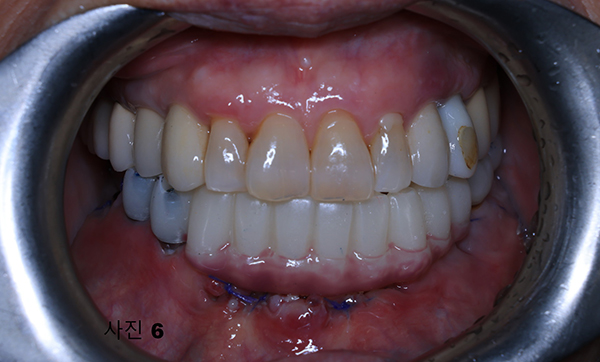

5개월후에 영구적인 티타늄과 지르코니아 보철물이 구강내 장착된 (사진5)와 x-ray(사진 6)모습이다.